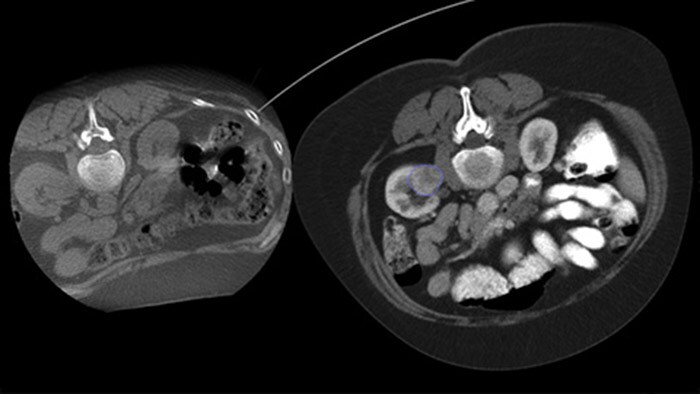

Dual View maakt de overlay van een 3D-beeld voorafgaand aan de procedure (CT/MR/PET-CT) op een intraprocedurele 3D CBCT Dual mogelijk om de laesies beter te visualiseren en toegang te krijgen tot cruciale informatie voor naaldplanning.

Heterogeniteit van laesies en gebrek aan opvallendheid beperken de kwaliteit van monsters en de uitvoerbaarheid van biopsieën onder echografie of conventionele CT. Sinds de toename van het gebruik van bevolkingsonderzoeken van de longen zijn longkankers in een vroeg stadium die zich manifesteren als kleine nodules vaker ontdekt dan ooit tevoren. 14,5% van een onderzochte populatie had nodules van ≤ 10 mm.1-2 Onze naaldnavigatietechnologie met CBCT verhoogt de precisie en maakt het mogelijk om nauwkeuriger op kleinere (<= 1 cm) of heterogene laesies te focussen met minder naaldherpositionering en bij een lagere dosis dan conventionele CT.1-2